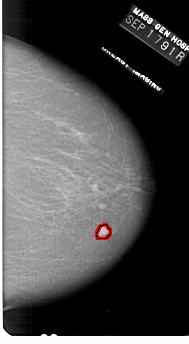

A_1727_1.RIGHT_MLO

RIGHT_MLO LINES 6511 PIXELS_PER_LINE 3451 BITS_PER_PIXEL 12 RESOLUTION 43.5 OVERLAY

FILE: A_1727_1.RIGHT_MLO.OVERLAY

TOTAL_ABNORMALITIES 1

ABNORMALITY 1

LESION_TYPE MASS SHAPE LOBULATED MARGINS CIRCUMSCRIBED

ASSESSMENT 5

SUBTLETY 5

PATHOLOGY MALIGNANT

TOTAL_OUTLINES 1